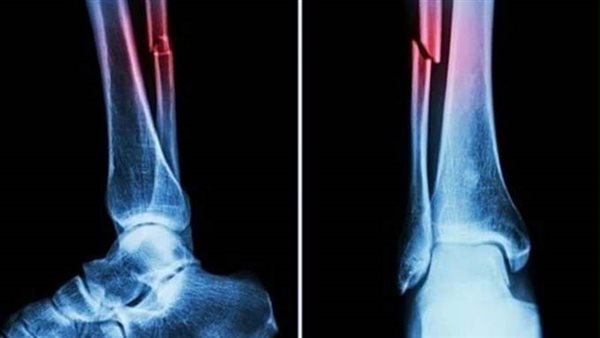

غراء العظام.. اختراع صيني يعالج الكسور في ثلاث دقائق

أعلن فريق بحثي في مقاطعة تشجيانج شرقي الصين عن منتج طبي جديد، "غراء عظمي" قادر على علاج الكسور وإعادة ربط شظايا العظام في ثلاث دقائق فقط، في خطوة وصفت بأنها اختراق علمي في عالم جراحة العظام، بحسب قناة "NDTV".

أكدت الاختبارات المعملية أن Bone-02 حقق نتائج جيدة من حيث السلامة والفعالية. في إحدى التجارب، أُجريت العملية في أقل من 180ثانية "ثلاث دقائق"، بينما استغرقت طرق العلاج التقليدية وقتًا طويلاً لزرع الشرائح الفولاذية.

وأظهرت التجارب التي أُجريت على أكثر من 150 مريضًا نتائج ناجحة، مما يزيد من إمكانية استخدامه كبديل للغرسات المعدنية التقليدية المستخدمة لتثبيت العظام. ويقول العلماء إنه قد يقلل أيضًا من خطر العدوى.